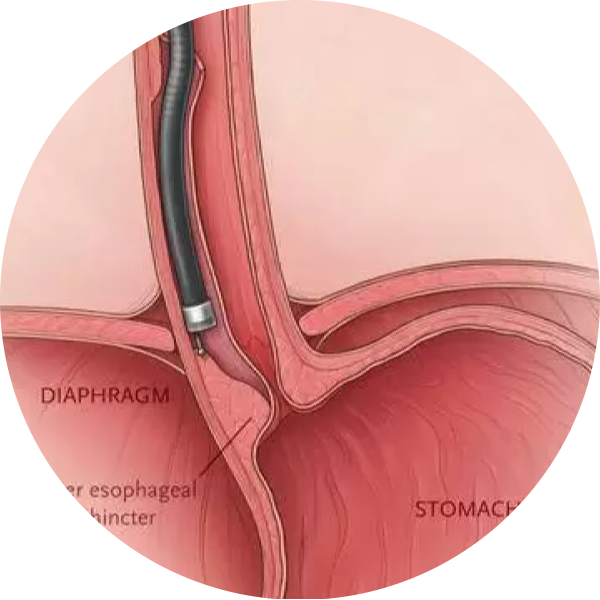

Endoscopic Anorectal Surgery is a minimally invasive surgical procedure used to treat conditions affecting the anus and rectum, such as hemorrhoids, anal fissures, or rectal prolapse. This technique uses an endoscope, a thin, flexible tube with a camera, which allows the surgeon to view the affected area on a monitor

Some of the common anorectal conditions treated with Endoscopic Anorectal Surgery include:

Persistent itching or irritation around the anus, which may be caused by hemorrhoids or other anorectal issues.

A noticeable lump or swelling around the anus, which may indicate hemorrhoids or other growths.

Difficulty controlling bowel movements or leaking stool, often seen in cases of rectal prolapse.